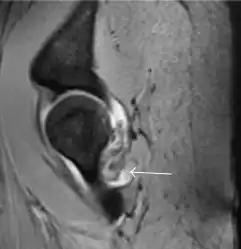

In adults, MRI is currently playing a definite role in the assessment of osteoarthritis. Although traditionally belonging to the arena of radiographs, the role of MRI has been stressed after the term femoral acetabular impingement was coined in 2003. Growing interest has been focused in accurate diagnosis of the acetabular and femoral morphological abnormalities that may lead to early osteoarthritis.[1]

MR imaging is considered paramount to these objectives, mainly when surgery is considered, due to the ability of MRI to portray the whole section of the femoral neck surface, as well as to image the labrum and articular cartilage.[1]

Diagnosis of impingement can only be achieved if, besides imaging findings, there are also clinical symptoms and positive impingement maneuvers.[1]

Most of the angles and measurements described in the plain radiograph section can be accurately reproduced on MRI. In addition, the superiority of MRI resolution with intra-articular contrast allows detection of labral and chondral abnormalities that may influence the choice of medical, percutaneous, or surgical management (Figure 9).[1]

Figure 9:

Intra-articular osseous causes of pain include several conditions: avascular necrosis (AVN), transient osteoporosis of the hip (TOH), tumors, and stress or insufficiency fractures. All these entities may present with a pattern of bone marrow edema characterized by decreased signal intensity on T1 weighted images and increased signal intensity on fluid sensitive sequences, such as fat saturated T2-weighted or STIR images. When there is no evidence of a focal lesion associated with the edema pattern, TOH is suspected. When a band of low intensity is seen inside the edematous area, the shape and length of this band become important. It is generally convex to the articular surface in the case of subchondral stress or insufficiency fractures, whereas it is concave, circumscribing all of the necrotic segment, in cases of AVN. When doubts do persist, gadolinium-enhanced MRI tends to show that the proximal portion beyond the band is enhanced in fractures but is not in AVN.[1]